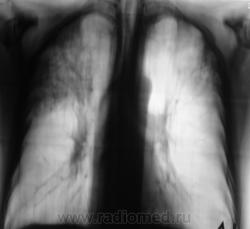

Вот, и мы так решили, с учетов ограничеснных возможностей нашей ЦРБ-ушки. Взял коллега фтизиатр "изображения", а также и изображения в динамике, а также необходимый "гарнир", и поехал в головное "фтизное" учреждение. В учреждении проконсультировали и выставили правосторонний инфильтративный. Ну и у нас считай - гора с плеч...

Пациента госпитализировали в областное противотуберкулёзное учреждение. Пролечили в течение месяца.... и выписали.

Произведен контроль после лечения. Заключение рентгенолога данного учреждения - "Со стороны органов грудной полости патологических изменений не выявлено".